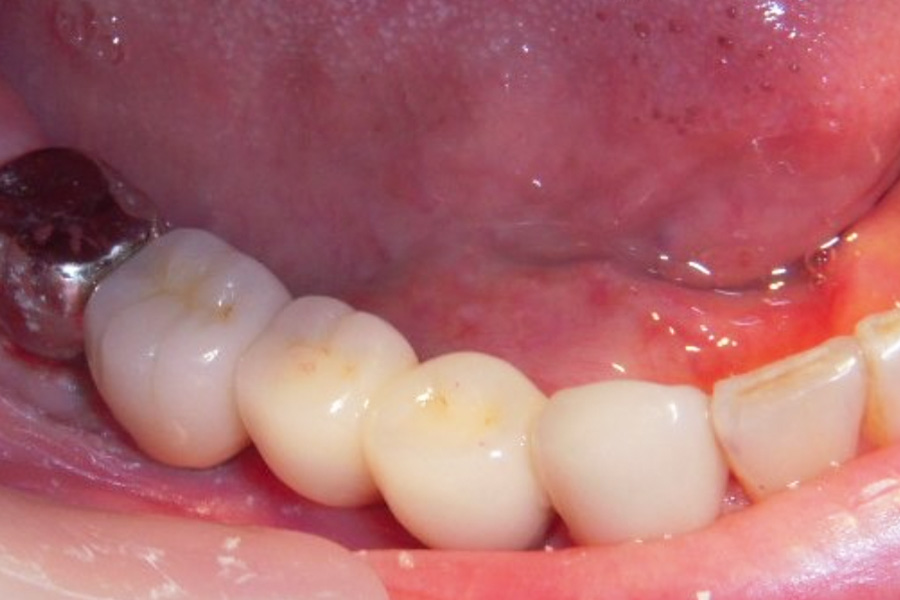

- スプリットクレスト(歯槽堤拡大術)

ジルコニア仕上げ

- 骨が細い為、骨造成が必要となる場合やインプラントの安定が得にくい可能性があるので、定期メンテナンスと自己ケアの両立が大切になります。